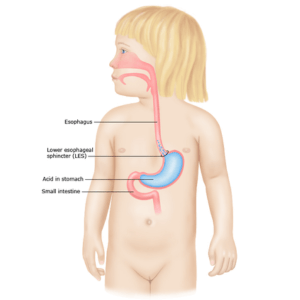

Gastro Oesophageal Reflux